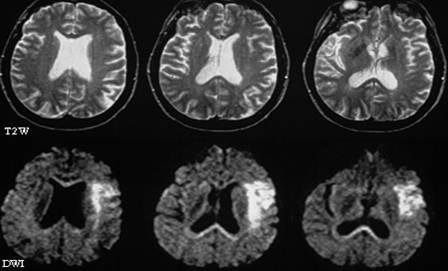

相较于“落魄”的过去,如今的放射科绝对是一众科室中的“土豪”:拥有三台DR拍片机,分别置于科室内、体检中心及体检车上,极大地拓宽了服务范围;当初的2排CT升级为德国进口的64排,且增加至2台,原本患者长达40秒的屏气如今仅需约10秒;核磁共振仪也由原来的国产低场更新为美国进口的GE新型1.5T高场,图象质量及扫描速度今非昔比,肺小结节等的诊断率大幅提升。

设备更新了,诊断范围及水平也紧跟其上。从前需省市级医院完成的穿刺活检,如今在科室人员经验积累及自我技能积极填充的基础上,已能够实现独立作业。科室目前已开展肺小结节重建、冠状动脉CTA(冠状动脉CT造影检查)、其他血管CTA(血管CT造影检查)等多个项目,且诊断水平居嘉兴市前列。正在筹备中的DSA项目将对血管介入疗法的实现起到举足轻重的推动作用,届时,水平将能提升至省级甚至国内先进。